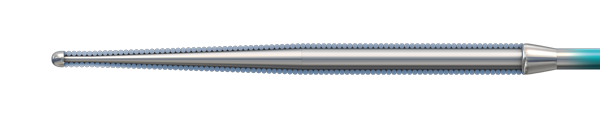

SAMURAI Guidewire

Workhorse wire with ICT for easy tip shaping, 1:1 torque, and optimal tactile feedback

- Inner Coil Technology

- Moderated hydrophilic coating